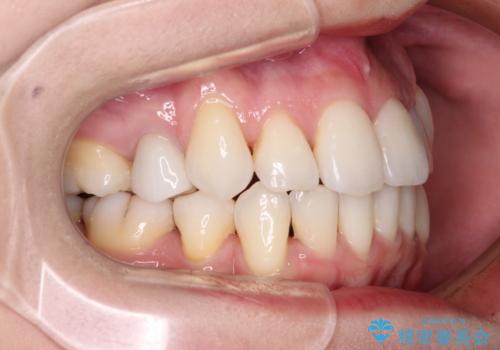

抜歯矯正は、2年半程度の治療期間を要することが一般的ですが、今回はセラミッククラウンによる補綴治療も含めて2年1ヶ月で終えることができました。

元々の歯並びが思い出せないくらい、きれいに仕上げることができました。